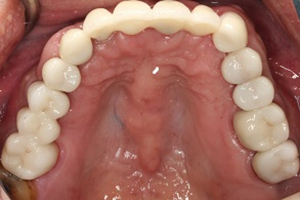

1. 經由多顆人工植牙及全瓷假牙的全口重建,牙周病治療讓病人恢復咬合的功能與美觀,也易於每日的清潔保養。

人工植牙與全口治療